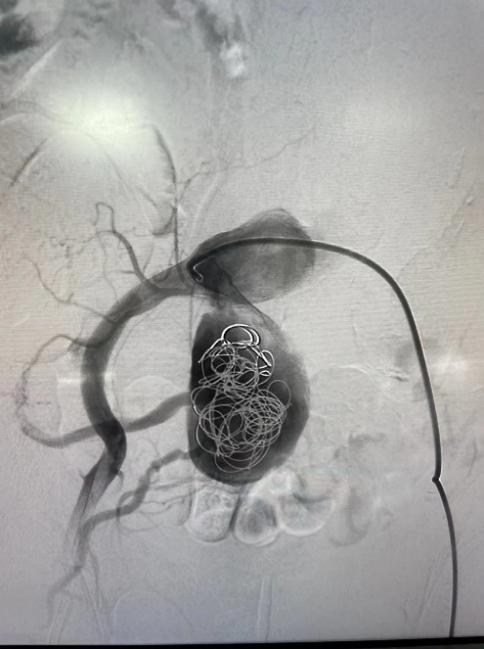

右側(cè)髂動脈動脈瘤栓塞術(shù)

2月28日,神經(jīng)內(nèi)科介入團(tuán)隊在西安交通大學(xué)第一附屬醫(yī)院血管外科蔡惠副主任的指導(dǎo)下成功為李伯實施了“右側(cè)髂動脈瘤栓塞+腹主動脈瘤腔內(nèi)隔絕術(shù)”,手術(shù)歷時2小時順利完成。

術(shù)后造影圖

術(shù)后,李伯再次造影提示支架貼合良好,且未發(fā)現(xiàn)內(nèi)漏、周圍臟器血管閉塞等并發(fā)癥。次日李伯就能下床活動,行走自如。目前,西電集團(tuán)醫(yī)院神經(jīng)內(nèi)科介入團(tuán)隊已成功為四名患者“拆除”腹腔“炸彈”。